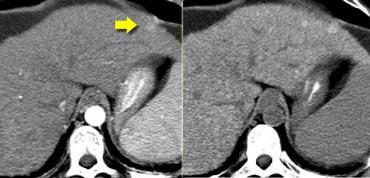

Tầm quan trọng của chụp cắt lớp không tiêm thuốc cản quang được minh họa qua trường hợp bên trái.

Trong thì động mạch, chúng ta thấy một cấu trúc tăng tỷ trọng ở phân thùy bên của thùy gan trái.

Hình ảnh này trông giống như một nốt ngấm thuốc rất gợi ý ung thư biểu mô tế bào gan giai đoạn sớm.

Tuy nhiên, nếu nhìn vào ảnh CCLVT không tiêm thuốc bên phải, chúng ta sẽ nhận thấy rằng đây không phải là hình ảnh ngấm thuốc. Đây chỉ là một nốt chứa sắt (nốt siderot) có tỷ trọng cao.

Chúng rất phổ biến và được ghi nhận ở tới 50% bệnh nhân xơ gan.